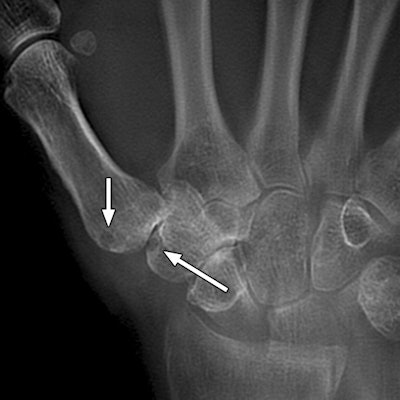

MRI has had more success in visually detecting bone erosion before the condition can be seen on conventional x-rays. Meanwhile, tomosynthesis has the ability to evaluate subtle fractures and joint surface, as well as image metallic implants.

Tomosynthesis and MRI detected significantly more bone erosions than conventional radiography, the researchers found. The detection rate for tomosynthesis was 36.1%, compared with 36.7% for MRI and 26.5% for digital radiography.

Based on the results, "tomosynthesis is far superior to radiography and is comparable to MRI for the detection of bone erosion in patients with rheumatoid arthritis," Aoki and colleagues wrote.